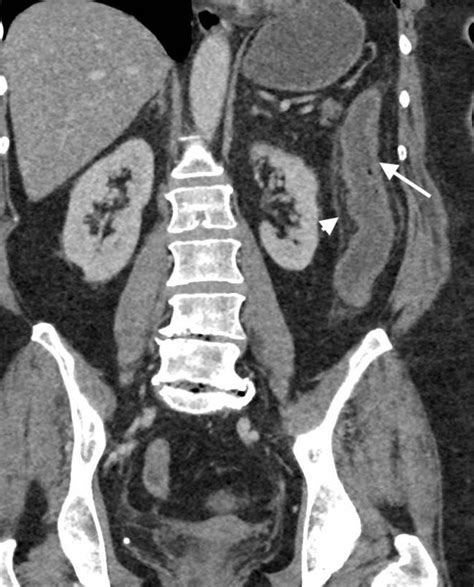

• CT Scan: A detailed imaging test that can provide a comprehensive view of the colon and surrounding tissues.